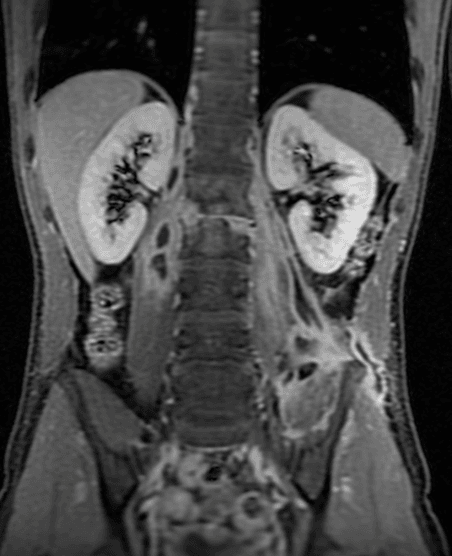

Figura 2.